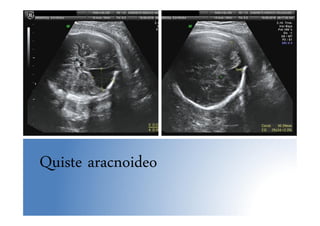

Quiste aracnoideo

Anomalías SNC • Anomalíasdetectables: holoprosencefalia lobar, displasia septo-óptica, lesiones destructivas (hemorragias, porencefalia, quistes), alteraciones proliferación y migración neuronal (microcefalia, macrocefalia, lisencefalia) • Microcefalia: PC < 3DE • Macrocefalia: PC > 3 DE • Lisencefalia: ausencia de circunvoluciones visibles en eco. Dx tardío pues no se desarrollan hasta finales 2º T • Otras: Agenesia parcial y total de CC